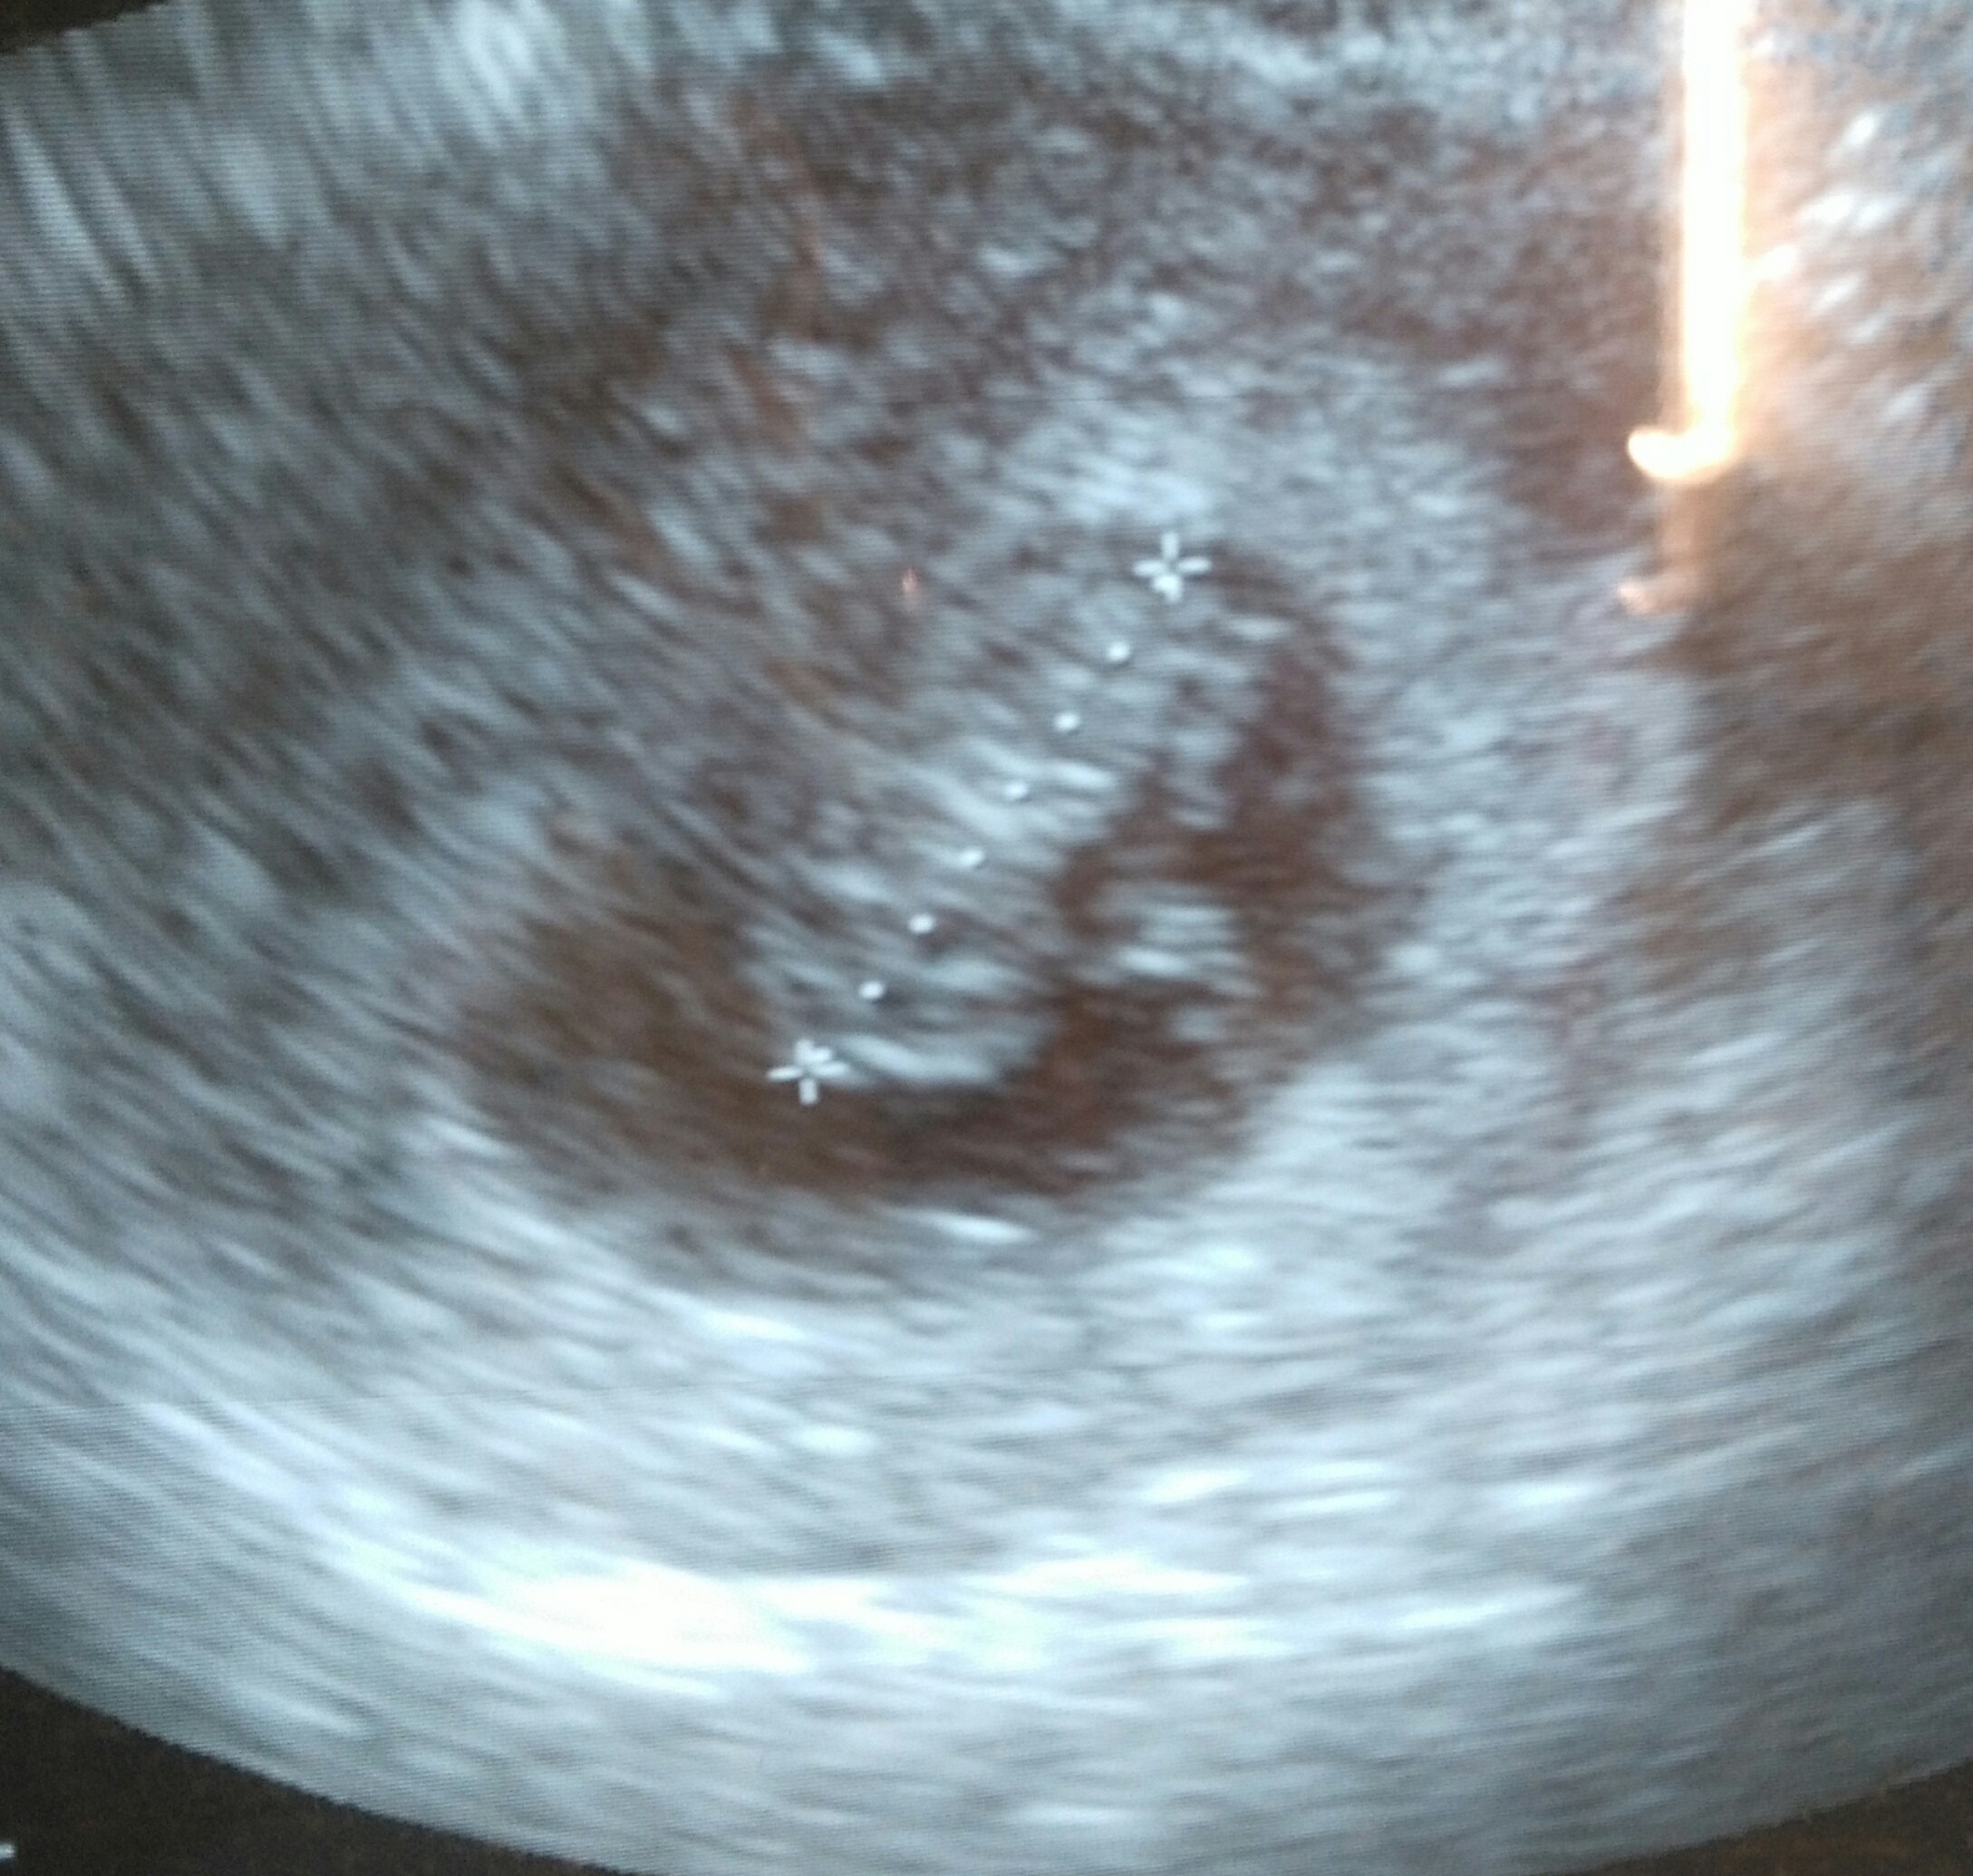

Ja już też po pierwszej wizycie. Jak na razie jest dobrze. Dzidzia okazała się o tydzień większą, choć nie wiem jak to możliwe. Poszłam 6t6d a ż rozmiarów był 8tc. Dzidzia 1,47cm i serduszko 150. A oto mój dzidziolek. Oczywiście płakałam bardzo. Nie wiedziałam czego się spodziewać po tej wizycie.

wydaje mi się że dzidiol wygląda duży na tym ujęciu akurat. Lekarka mi mówiła, że dzidziol jest zaznaczony strzałką, a nad nim ciałko żółte, które wygląda jak głowa i daje wrażenie dużego bejbika, bo z długości 1,47cm to właśnie wypada ok 8tc.